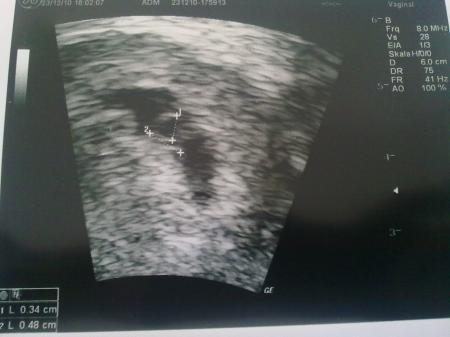

Das ist ja eine nette Idee!! Also ich habe am 12.Dezember positiv getestet und hatte dann meinen ersten FA-Termin am 23.Dezember! Da war ich dann in der 6.SSW und mein kleiner Mann war 0,48cm klein! Das Herzchen konnte ich da auch schon schlagen sehen! Glg, Claudia

Bild zu

also ich hatte am 20.12 einen test gemacht und am 21.12 hatte ich gleich einen termin, da war ich in der 8. woche und da hab ich dieses US bild bekommen: